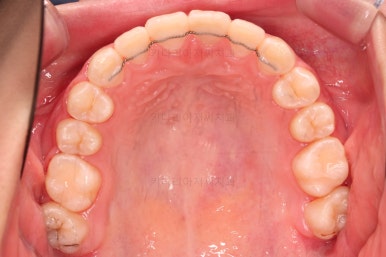

1. 초진

초진 시 입안의 모습입니다.

눈에 띄는 부분은 당연히 앞니가 삐뚤고, 앞니 하나가 앞으로 튀어나온 모습인데요.

자세히 관찰해 보면 다른 문제점들이 보입니다.

우선 위아래 앞니가 깊숙히 맞물려 있는 과개교합 양상인데요.

이번 환자분은 어금니가 위아래가 지그재그 서로 엇갈려 꽉 끼이는 교합이 아니라 1대1로 치아가 부딪혀 있는 상태였습니다.

✅ 악궁 확장

악궁확장 내용이 나올 때면 매번 말씀 드리는 내용이 있습니다.

치열이 삐뚤었다고 공간확보 목적으로 악궁확장을 하는 건 아니다.

아래와 위의 턱뼈의 크기 부조화가 있을 때 위턱을 넓혀주는 것이 악궁확장이며, 저희 부산청소년교정치과 키다리아저씨치과에서는 정교한 3차원 CT분석을 이용해서 골격의 크기를 비교해서 꼭 필요한 경우에 악궁확장을 해주게 됩니다.

당연히 확장을 하면 부가적으로 공간확보가 일정 부분 더 잘된다는 효과도 있지만 공간확보를 위해서 턱뼈의 크기가 조화로운데도 불구하고 악궁확장을 한다면 또 다른 좋지 못한 결과가 생길 수 있어서 매우 조심스러운 평가가 선행되어야 합니다.

이번 환자분은 악궁확장이 필요한 케이스였으며, 청소년이었기 때문에 별도의 미니스크류 없이 일반 확장장치를 이용했습니다.